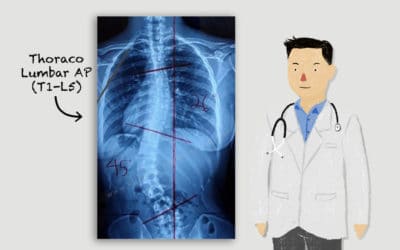

Pentingnya Rontgen Tulang Belakang Untuk Pemeriksaan Skoliosis – Ini 3 Tujuannya!

Pemeriksaan rontgen tulang belakang dilakukan saat anak mulai menunjukkan tanda tanda skoliosis Penyembuhan penyakit skoliosis dipengaruhi oleh usia saat pertama kali mendapatkan terapi brace. Semakin cepat skoliosis dideteksi, maka semakin cepat skoliosis...